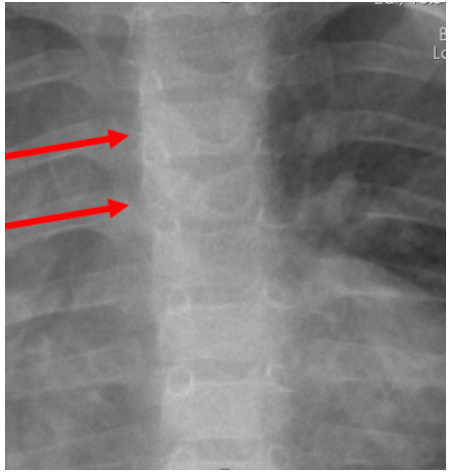

Alagille syndrome (AGS) is an autosomal dominant disease with multisystemic involvement.1 The disease occurs as a result of mutations in the Notch signaling pathway.2 In AGS, the liver (biliopathy, cholestasis), heart (eg, peripheral pulmonary stenosis), skeletal system (butterfly vertebra (Figure 1), hemivertebra, recurrent fractures), eyes (posterior embryotoxon, anomalies affecting the iris and retina), kidney (renal tubular acidosis), and brain (vascular anomalies in the brain) are the most affected areas.3-7 Patients with AGS have characteristic external appearance, which can include prominent forehead, deep-set eyes with moderate hypertelorism, pointed chin, and straight nose with a bulbous type2,8 (Figure 2). Prevalence of AGS is 1 in 70 000 births.9 The clinical presentations of AGS can vary. In 30% of cases, chronic liver failure, portal hypertension, or widespread itching can lead to decreased quality of life and requirement for liver transplant.10,11 Heart involvement also accompanies AGS at a rate of 90%, and this degree of involvement has been associated with early mortality in AGS. Long-term survival is mostly determined by liver involvement. During liver transplant, hemodynamic changes due to the patient’s cardiac involvement are the most important factor determining the outcome of the surgery.12 Here, we report the results of 10 pediatric patients who underwent liver transplant due to AGS at our center.

Figure 1. Butterfly Vertebrae (arrows)